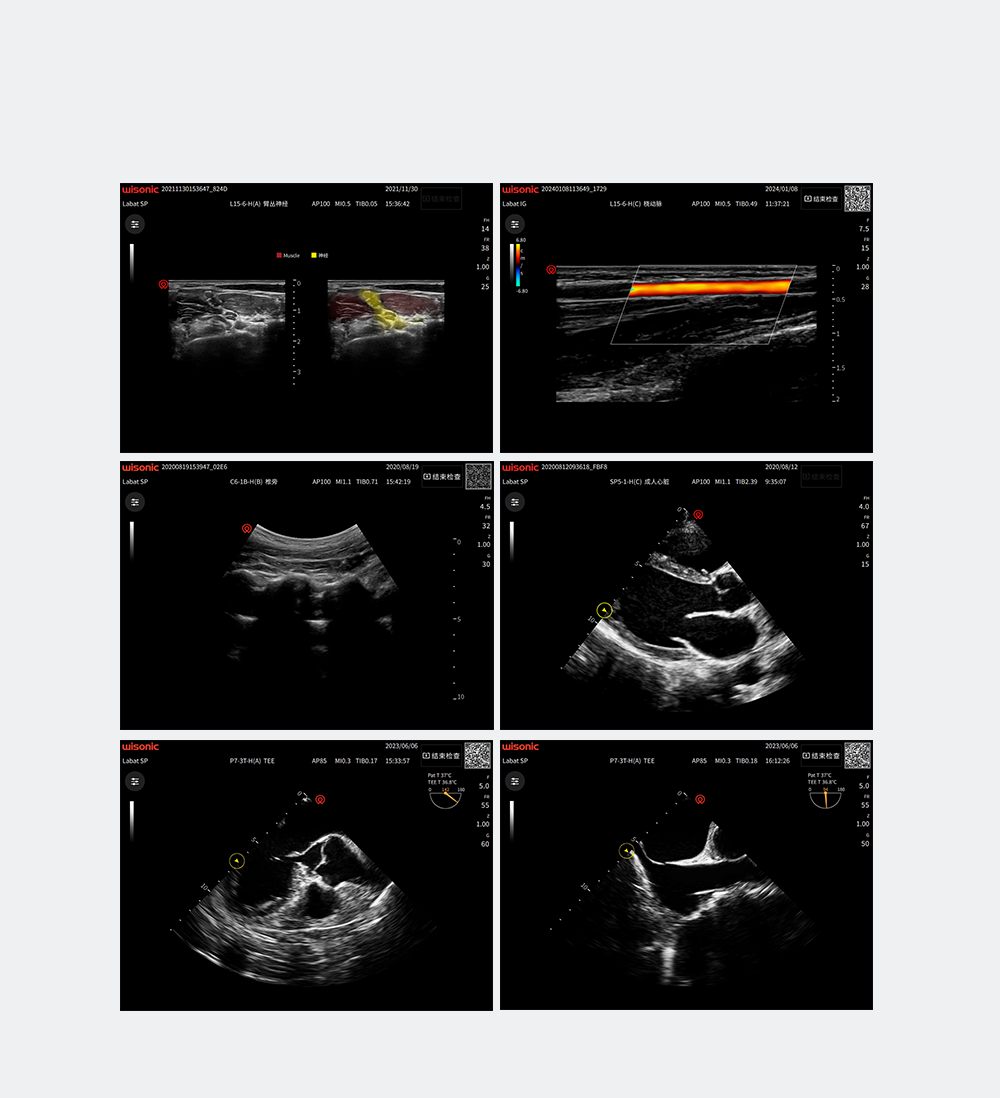

wiNerve

Reconnaissance intelligente des nerfs par IA

Reconnaissance en temps réel

Soutenir plusieurs nerfs

Excellentes images cliniques

Photos d'applications